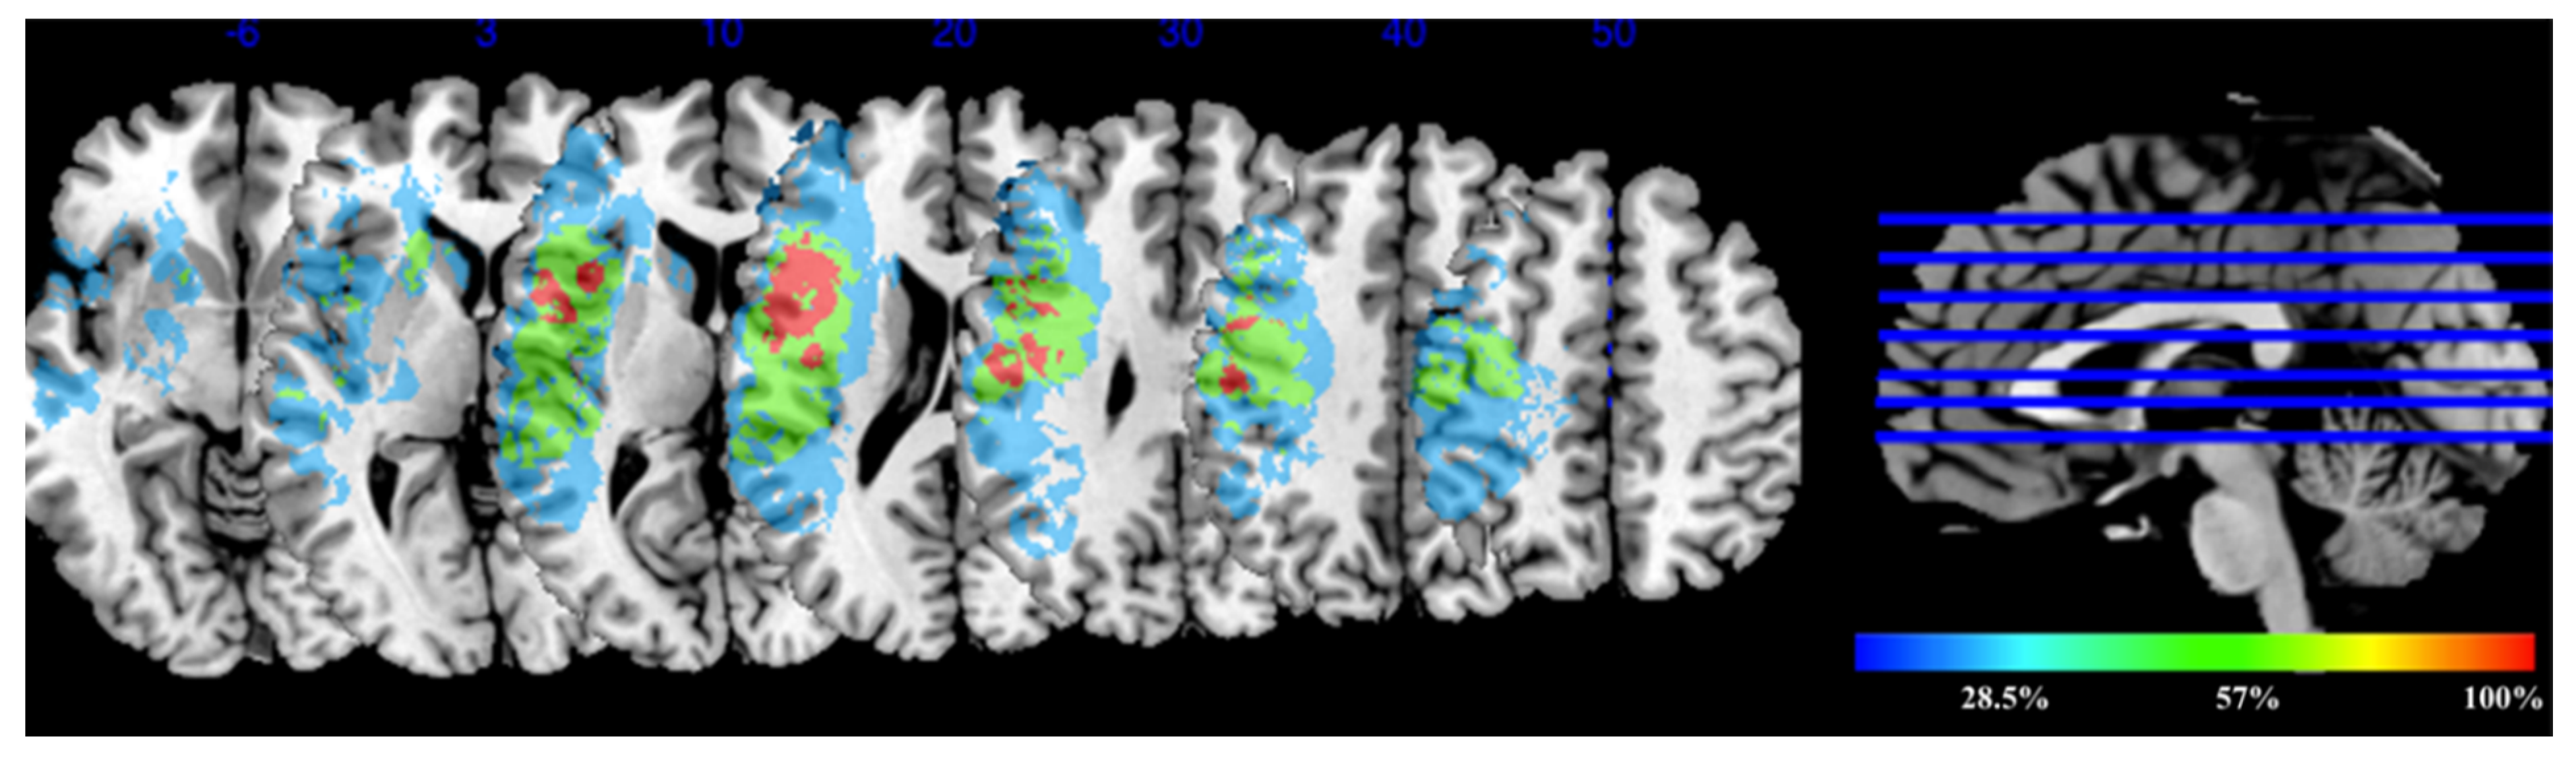

3.2. Lesion Overlay Map for the Experimental Group Receiving tDCS

3.3. Diffusion Data